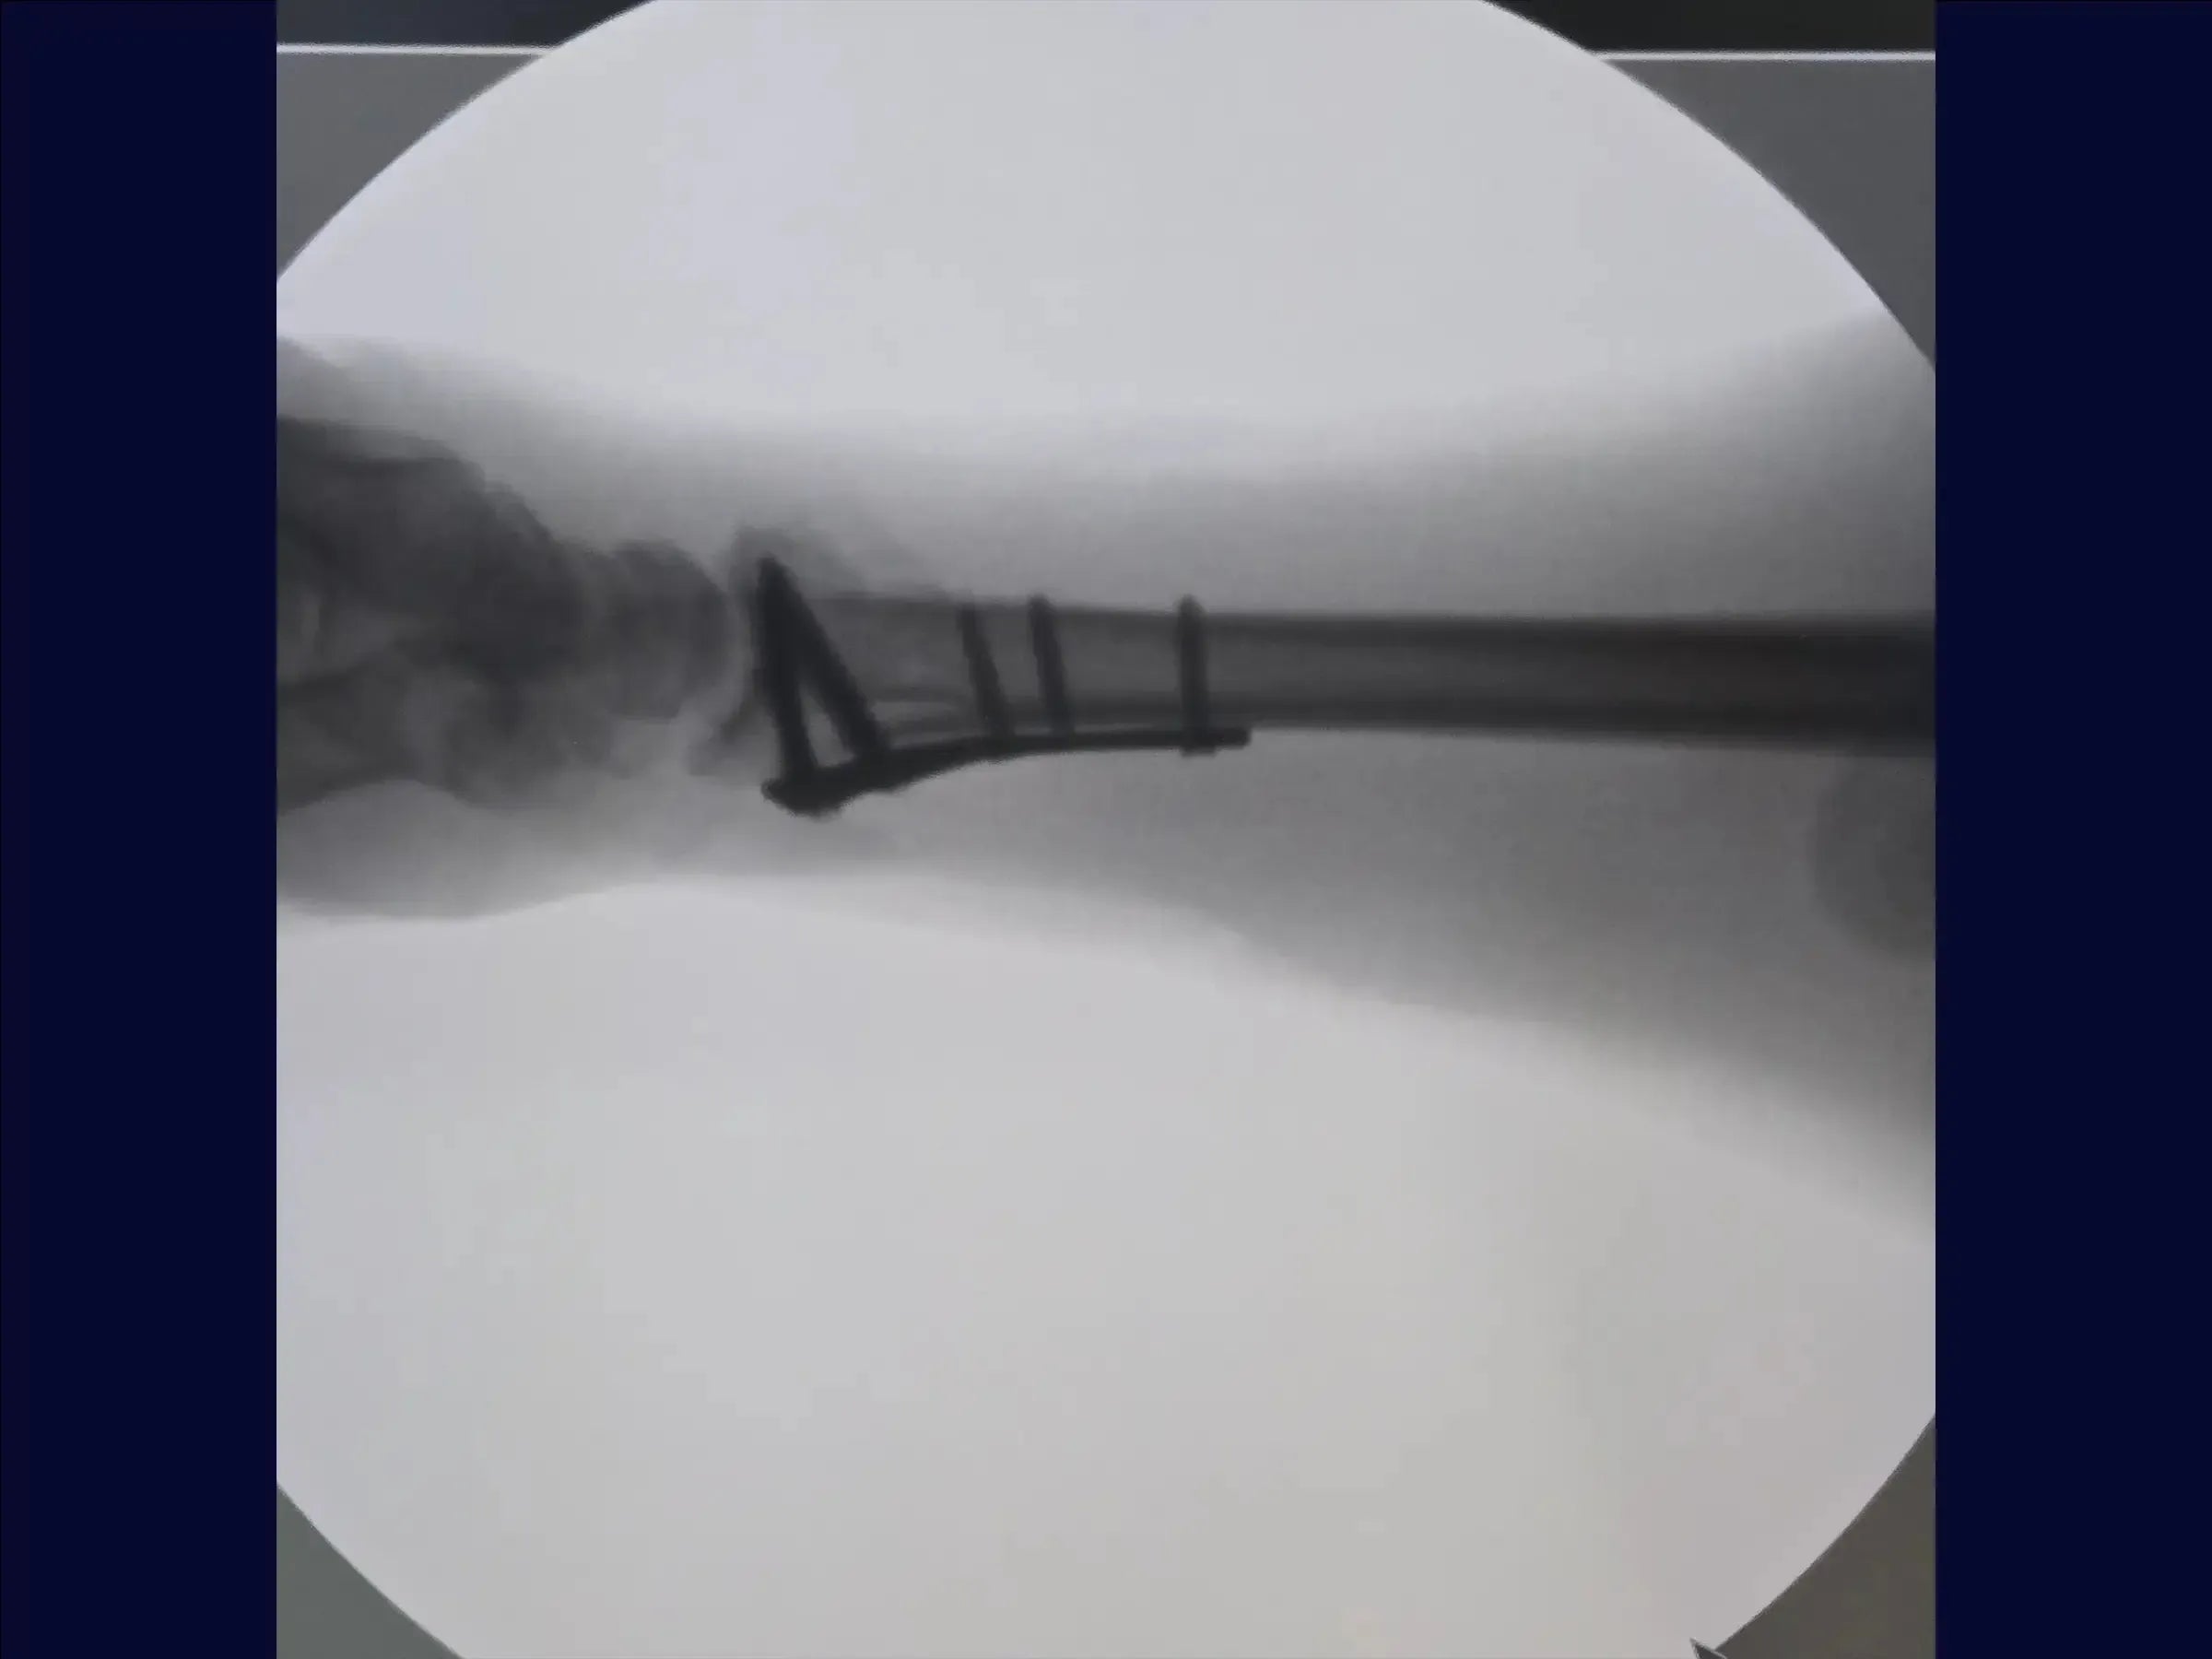

- Exposição do Rádio e Implantação da Placa: O rádio é exposto, e um descolador é utilizado para preparar o leito da placa. Com a fratura já reduzida pela fixação provisória, a colocação dos parafusos deve respeitar a inclinação radial para evitar que fiquem intra-articulares. É recomendado manter a redução manualmente ou usar fios adicionais para evitar perda de redução.

- Fechamento e Resultados: O acesso através do pronador quadrado é suturado para cobrir a placa. O resultado final é satisfatório, com parafusos bem posicionados, inclinação radial mantida e fratura bem fixada. O fechamento é realizado por planos até a pele.